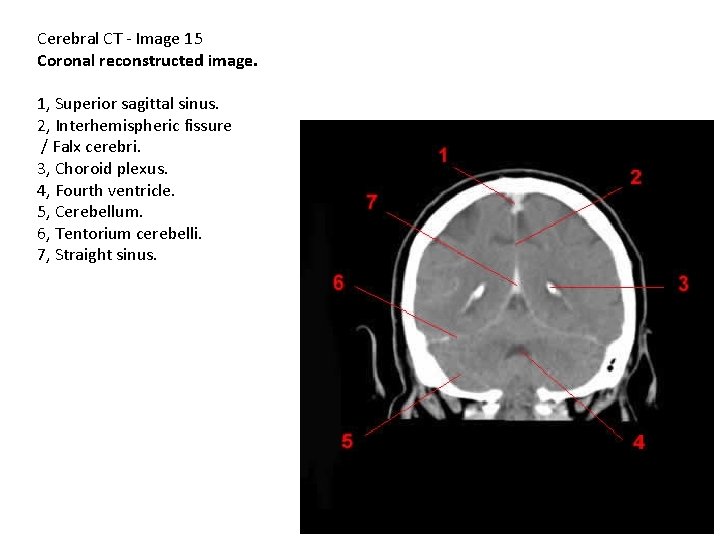

Cerebral CT - Image 15 Coronal reconstructed image. 1, Superior sagittal sinus. 2, Interhemispheric fissure / Falx cerebri. 3, Choroid plexus. 4, Fourth ventricle. 5, Cerebellum. 6, Tentorium cerebelli. 7, Straight sinus.